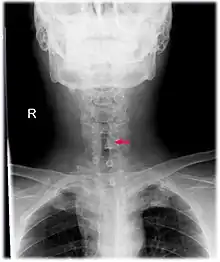

| Neck AP x-ray of patient with post-intubation subglottic stenosis, as shown by the narrowing in the tracheal lumen marked by the arrow. | |

Subglottic stenosis is a congenital or acquired narrowing of the subglottic airway.[1] It can be congenital, acquired, iatrogenic, or very rarely, idiopathic. It is defined as the narrowing of the portion of the airway that lies between the vocal cords and the lower part of the cricoid cartilage. In a normal infant, the subglottic airway is 4.5-5.5 millimeters wide, while in a premature infant, the normal width is 3.5 millimeters. Subglottic stenosis is defined as a diameter of under 4 millimeters in an infant. Acquired cases are more common than congenital cases due to prolonged intubation being introduced in the 1960s.[2] It is most frequently caused by certain medical procedures or external trauma, although infections and systemic diseases can also cause it.

CT scans and MRI (magnetic resonance imaging) can help in diagnosis. X-rays can determine the location and size of the narrowed airway portion. Optical coherence tomography (OCT) can help observe the progression of the injury. Esophageal pH monitoring can help detect any acid reflux, which can worsen the condition. An endoscope can be inserted and used to see the vocal cords, airway, and esophagus. Spirometry is a useful way to measure respiratory function. People affected by subglottic stenosis have a FEV1 of over 10.[2]